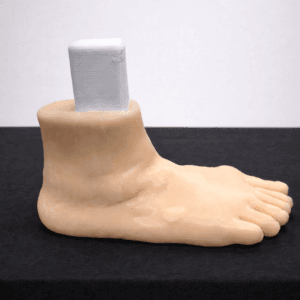

| Pathology | Pes Cavus |

| Procedure | Cole Osteotomy, Dwyer, Lateralizing Calcaneal Osteotomy, Metatarsal Dorsiflexion Osteotomy |

| Area | Midfoot |

| Modularity | Single-piece |

| Material | Opaque |

Pes Cavus – Bone Model